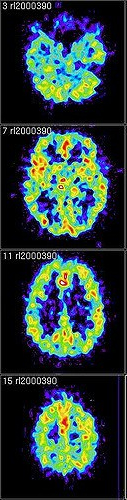

Though origination of this myth is largely unknown (and is sometimes attributed to Einstein), it is so wide-spread that it even has its own Wikipedia article! However, it is wholly false. In truth, we use 100% of our brains throughout an average day [1]. At any point, different regions of the brain may be more or less active, but there is not typically a region of the brain that is completely nonfunctional [2]. A portion of the brain’s function is to control automatic processes such as your heartbeat, blinking, and breathing. However, even when you’re asleep, there is more brain activity than just in the brain stem (which controls involuntary functions). Every area of the brain serves a different, important purpose –processing your senses, critical thinking, muscle control, movement, and memory, to name a few. Additionally, if 90% of our brain was not in use, brain injuries would not be such a serious issue. Instead, we know that even small injuries to the brain can have detrimental and lasting impacts!